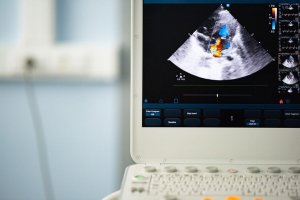

During the checkup they might use a stethoscope to be able to hear the irregular heart palpitations and, also, for signs of a heart murmur. After that, to verify that you have a bicuspid aortic valve, they’ll do an echocardiogram which helps to evaluate how the heart is working.

Additionally, it’s important for all the close relatives of the person with a bicuspid aortic valve to get an echocardiogram to make sure everything is okay. The reason is that this congenital defect can be hereditary. Due to this, relatives should make sure their valves are working properly.